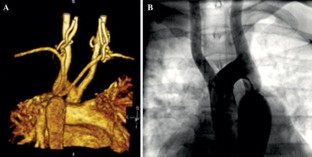

Acute left ventricular (LV) or right ventricular (RV) dysfunction during repair of coarctation of aorta (CoA) is rare. Well-developed collateral circulation between branches of both the subclavian arteries (SCAs) and upper descending thoracic aorta decompress LV and prevents acute rise in afterload. An adult patient presented for CoA repair. On chest X-ray, rib notching was not seen. Magnetic Resonance Imaging showed about 7 mm long CoA distal to the origin of left common carotid artery. Reconstruction images of distal arch and descending thoracic aorta showed origin of both the SCAs from CoA segment. Transthoracic echocardiography showed 1.3 cm atrial septal defect (ASD), left to right shunt, moderately severe mitral regurgitation (MR), dilated RV, and severe pulmonary artery hypertension (PH). During cardiac catheterization, the peak gradient across CoA was 60 mmHg. On aortic-root angiography, both the common carotids and the distal arch opacified simultaneously, the CoA segment and the distal aorta opacified a little later. Both the SCAs were filling retrograde. A unique anatomy in which aortic-clamping proximal to CoA and both the SCAs would increase flow to spinal-cord as clamping of the SCAs will stop stealing of blood into the CoA but potentially increase LV afterload, MR, left to right shunt across ASD and RV volume and pressure load depending on the magnitude of flow across the CoA. The increases in LV afterload, MR, and RV afterload and volume overload were managed by controlled phlebotomy and fine-tuned by manipulating inhaled isoflurane concentration whereas the Transesophageal echocardiography (TEE) monitored and guided the management.

Fig. 1